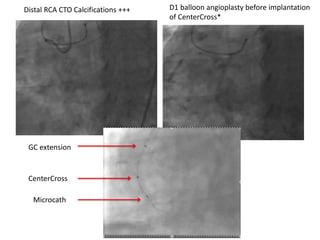

CenterCross

Microcath

GC extension

Distal RCA CTO Calcifications +++ D1 balloon angioplasty before implantation

of CenterCross*

Crossing of guide wire then microcatheter Final result after 3 Stents

• Must be use with a balloon

risk of coronary dissection